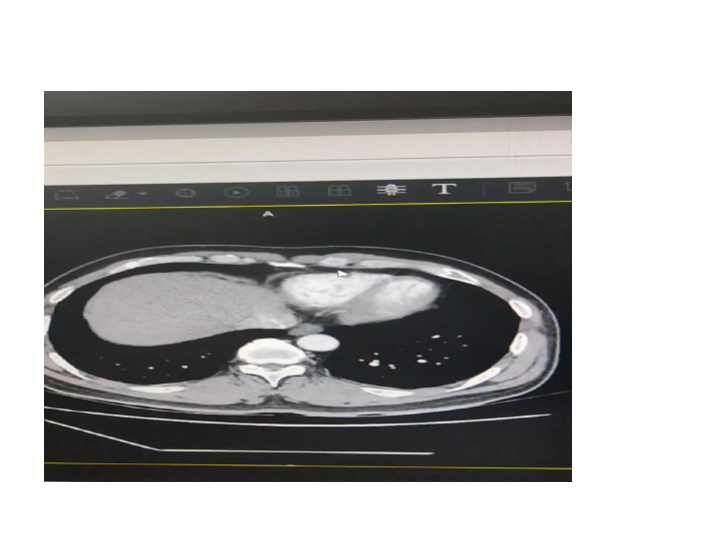

腹部外伤急救